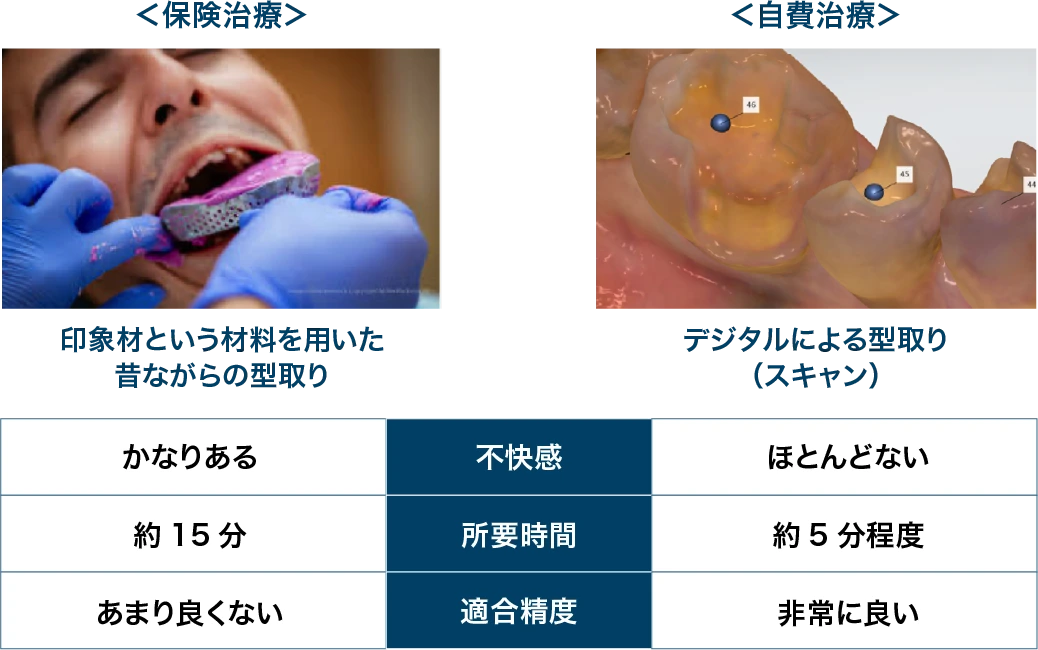

保険診療と自由診療では同じクラウンを作製するので、型取りの方法・精度・審美性・強度・長期安定性・保証期間などが異なります。

| 保険治療 | 自由診療 | |

|---|---|---|

| 型取り | 印象材と呼ばれる粘土のような材料で型取りを行います。 | 口腔内スキャナと呼ばれる最新の方法で型取りをおこなうため、不快感がありません。 |

04.型取りの違い